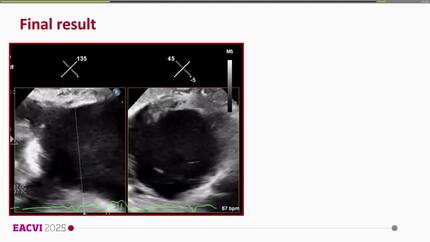

Percutaneous removal of right ventricular papillary fibroelastoma

Percutaneous excision of failed MitraClip in the tricuspid valve position